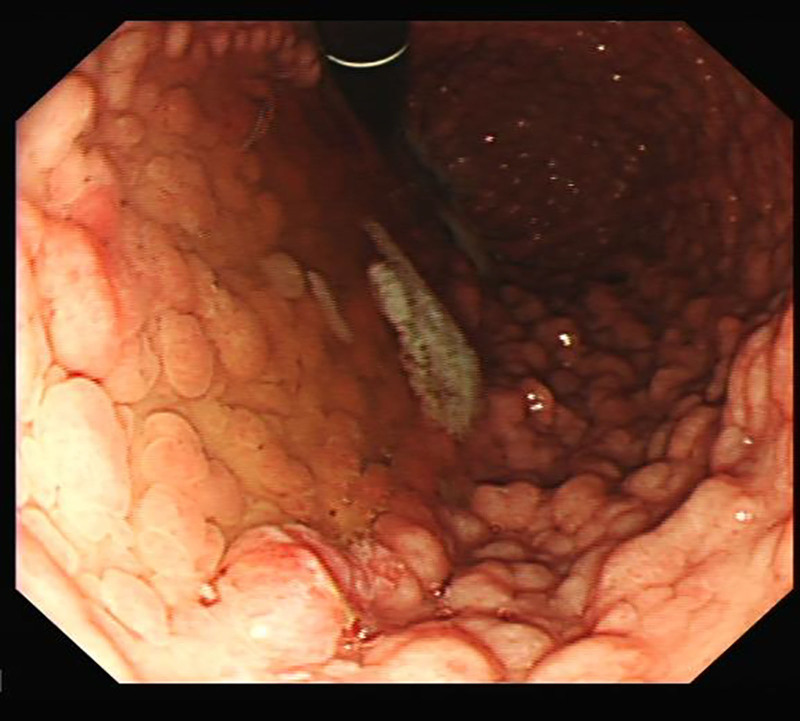

Objectives and study: Patients with familial adenomatous polyposis (FAP) have a propensity to form not only large bowel polyps but also upper gastrointestinal (GI) polyps with malignant potential. International guidance suggests that upper GI screening need not begin until patients are at least into their twenties. It is our experience that patients develop upper GI polyps long before this point which have the potential for malignant change.

Methods: A prospective record of all upper GI endoscopies in children (aged 9 to 17) with FAP was kept across a 12-year period by 1 surgeon in our center. For each scope performed, we recorded the location, histology, and treatment of upper GI polyps.

Results: Twent-eight patients aged 9 to 17 underwent a total of 48 esophagogastroduodenoscopies across a 12-year period. Thirty-eight esophagogastroduodenoscopies (79%) identified at least 1 gastric or duodenal polyp in 22 (79%) patients; 10 (36%) patients had gastric adenomas. Eight (29%) patients showed very high numbers of polyps. All 21 patients who had duodenal polyps had adenomas. None had yet developed malignancy, but 1 patient required extensive polyp excision and one is awaiting endoscopic mucosal resection.

Conclusion: Our results demonstrate that young people with FAP are at the risk of developing upper GI polyps long before current guidance suggests screening the upper GI tract. We advocate for screening of the upper GI tract to start along with colonoscopy and happen at the same sitting for pediatric and young adult patients with FAP.